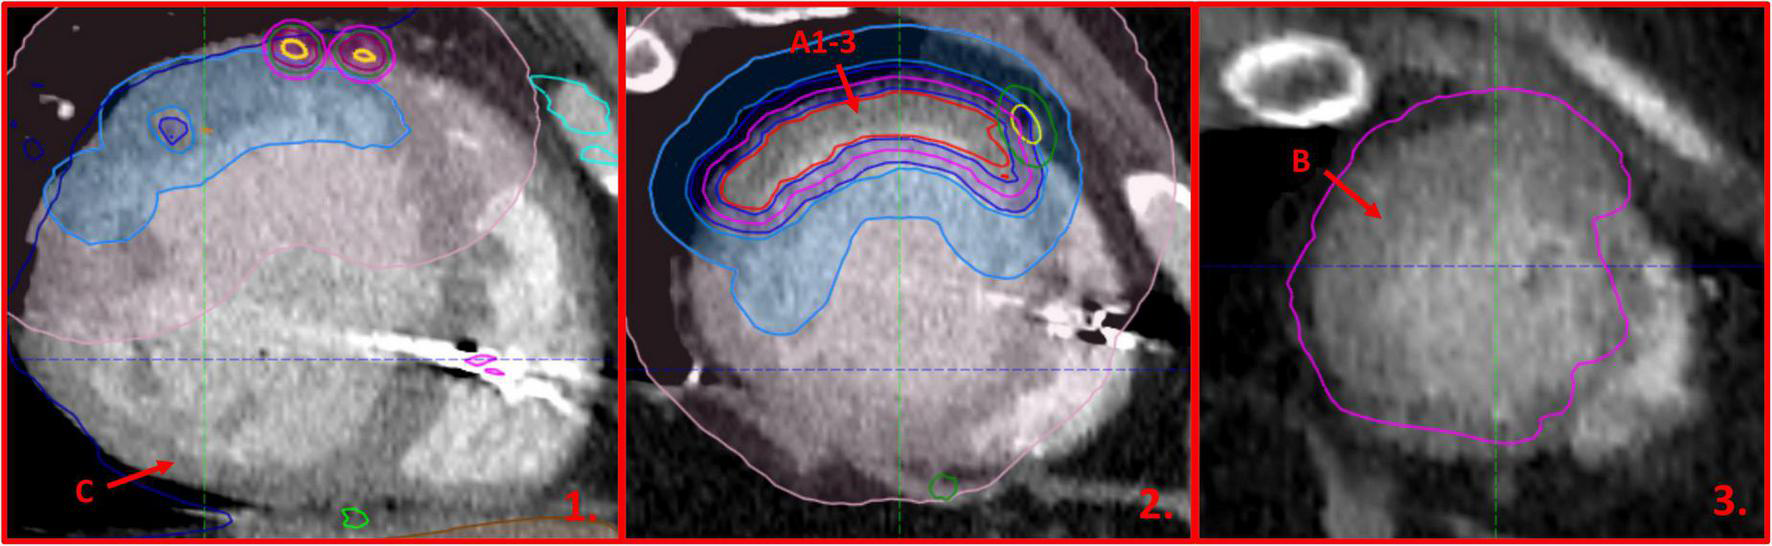

The Clinical Target Volume (CTV) measured 42.8 cc and included the whole thickness of the myocardial wall in the region of interest located in the anterolateral part of the left ventricle. The irradiated region was marked by late electrical potentials localized in the akinetic, post-ischemic part of the anterolateral wall of the left ventricle, likely caused by a terminal occlusion of the left anterior descending artery due to advanced atherosclerosis (Figure 2). No prior RFA was performed in the irradiated region. The CTV was expanded by a uniform margin of three mm to account for residual organ motion and positioning uncertainties, resulting in an 88.7 cc Planning Target Volume (PTV).

A series of four routine samples from both ventricles and 17 further samples from regions of interest were taken by the pathologist (JN). The acquisition of the samples was directed by the attending radiation oncologist (MM) and two cardiologists (MS and MC) with the aid of pre-treatment cardiac CT fused with radiotherapy-planning structures, adjusted to match the geometry of the following slices through the specimen (Figure 5).

FIGURE 5

Cardiac-CT images adjusted to the slices performed during the autopsy of the explanted heart. Blue outline (1-2) marks the region irradiated with approximately 7.5 Gy, while violet outline (2-3) shows the planning target volume to which 25 Gy was prescribed. The arrows and letters indicate the approximate localization of the pathology specimens referenced in the article.

The PTV was irradiated up to a total dose of 25 Gy in one fraction. Sparing of organs at risk had higher priority over delivering a homogenous dose to the whole volume of PTV (Figure 3). The radiotherapy plan was prepared using the Volumetric Modulated Arc Therapy technique and consisted of three arcs. The radiotherapy delivery was performed on a Varian EDGE linear accelerator. The patient positioning verification was performed with DIBH Cone Beam CT (CBCT). The whole treatment session performed with the DIBH technique took 33 min including 18 min for the initial positioning.

FIGURE 3

Color-wash representation of the dose distribution within the irradiated heart, ranging from 20 Gy (blue) up to a maximum dose of 30.7 Gy (red). The coronary artery sparing is well-visible in the upper part of the upper-left sagittal projection.